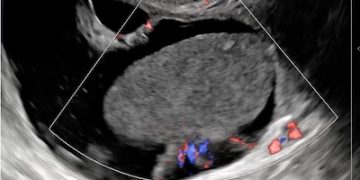

Casi del Mese di Dicembre 2024

Cari soci, finalmente on line le soluzioni dei casi del mese di Dicembre. Grazie a Sara Zullino e Mara Albanese!! Caso 1 - video [pdf-embedder url="https://www.sieog.it/wp-content/uploads/2024/12/Casodelmese_Dicembre2024caso-risposte_gineco.pdf"...